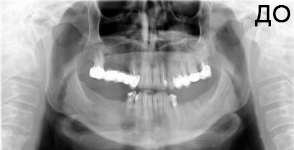

4 работы в портфолио

Удаления зубов любой сложности. Пародонтология (закрытый, открытый кюретаж, лоскутные операции, рецекция верхушки корня, вестибулопластика, френулотомия, френулоэктомия). Переостотомия, вскрытие абсцессов и других воспалительных процессов. Цистотомия, цистэктомия. Имплантология (установка имплантатов различных систем с осложненными анатомическими условиями, направленная костная регенерация, открытый синус-лифтинг, закрытый синус-лифтинг, пластика альвеолярного гребня).

Акопян Антон Владимирович: портфолио (4)